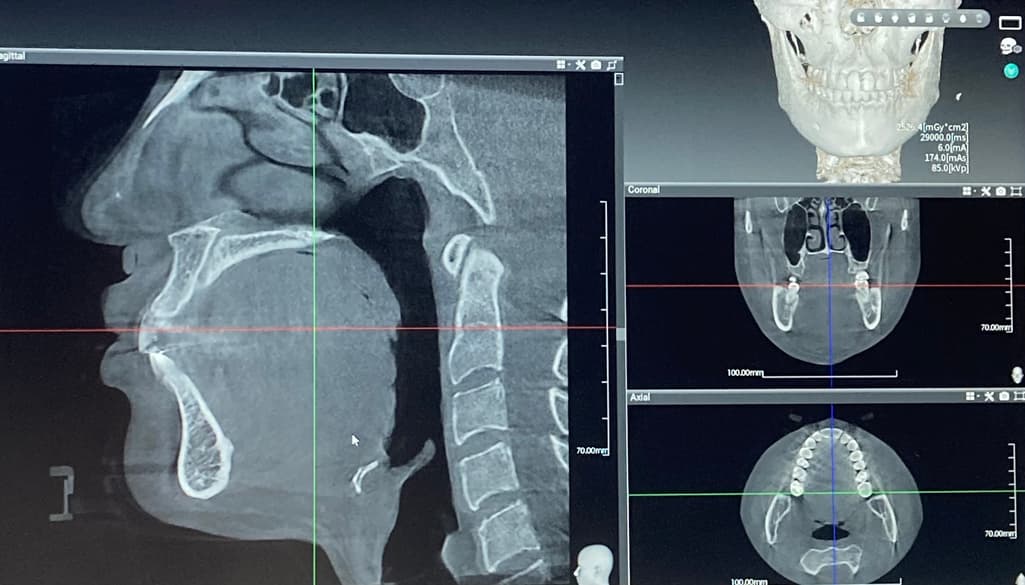

사진으로는 정확한 진단 불가능하며 병원 방문하셔서 직접 육안으로 진료 보셔야 합니다

사진은 입체감이 떨어져서 파악이 불가해요. 전후 모양을 비교 해 볼 수 있는 것도 아니구요